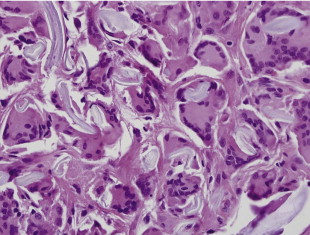

Additional causes of localized inflammation in addition to suture granuloma include granuloma formation from foreign body ( Figure 15.5 ). Common causes include powder from surgical gloves, makeup including eye shadow and mascara, retained ophthalmic ointment, or liquefied fat following blepharoplasty. These are typically diagnosed at the time of biopsy with confirmation by appearance of foreign body on polarized light. Additionally, lipogranulomas can form which are different than non-caseating granulomas with respect to localized inflammatory processes around fat cells. Oil cyst can also occur either from liquefied fat or localized fibrosis and inflammation around ophthalmic ointment. Treatment includes conservative management and the majority of patients spontaneously resolve with time and treatment of underlying inflammation with low dose steroids including a Medrol Dose Pack.